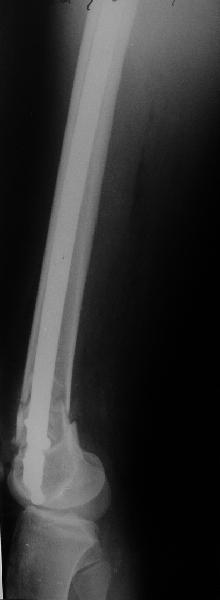

Re: Перелом диафиза и мыщелка бедра

I> Насчет того, чтобы винты, фиксирующие мыщелок являлись одновременно

I> блокирующими не согласен - далековато гвоздь забивать придется.

А в чем проблемы? Пример в приложении.